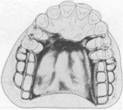

Fig. 5-35 Anatomic replica palatal major connector for a Class II, modification 1, partial denture. Anterior border avoids coverage of anterior rugae; posterior border lies well back on immovable hard palate, crossing midline at a right angle. Total contact provides excellent auxiliary retention without objec­tionable bulk.